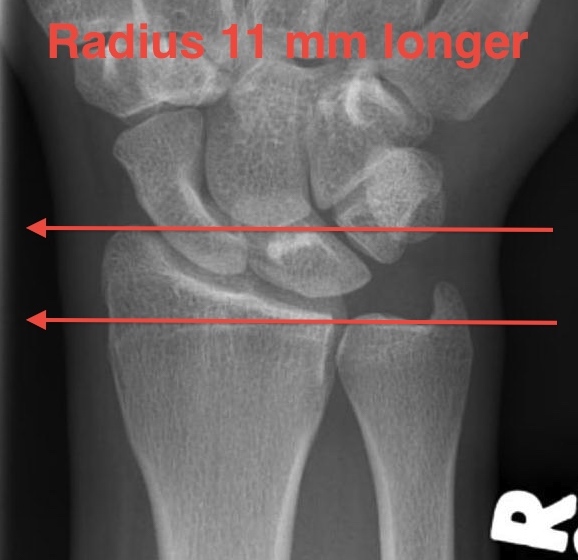

Radial angles

| Volar tilt mean 11° | Radial inclination mean 22° | Radius mean 11 mm longer than ulna |